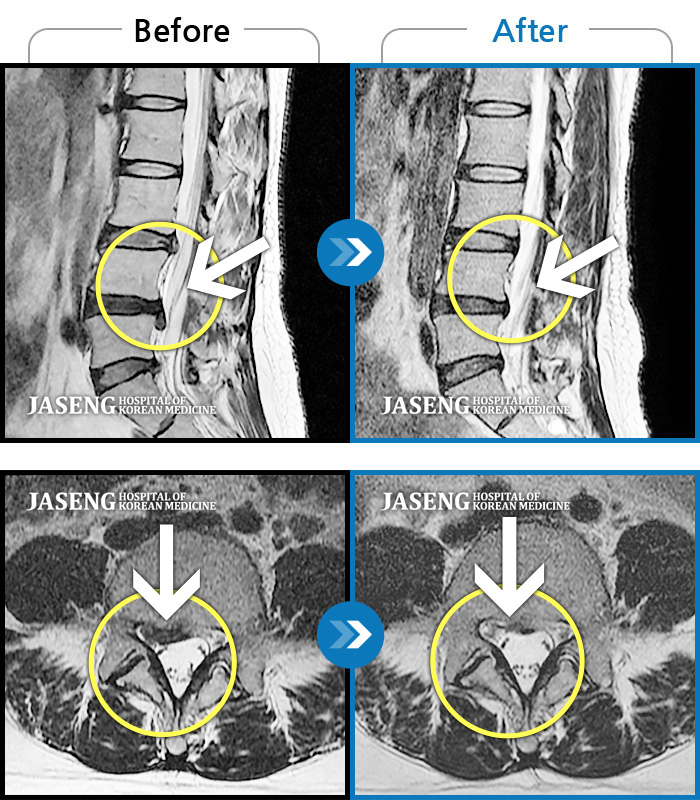

허리디스크

인천 · 조남훈 원장

허리가 너무 아프고 다리가 저려요.

촬영시기

2018.04.23 ~ 2025.12.05

2025.12.19